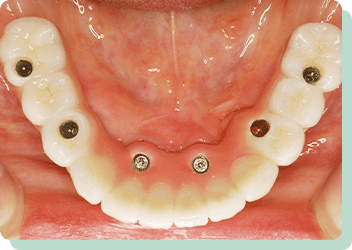

上の歯は残っており、下の歯は全て抜けてしまったケースです。総入れ歯にした場合、受圧加圧のバランスが悪く、何でも噛める入れ歯を作ることは困難です。歯があった時のように食べれるようにという希望でしたが、十分な満足を得ることが出来ました。術後10年以上経過しましたが、問題なく機能しています。

リスク:疼痛・咬合時痛・冷水痛・出血・インプラント手術による歯ぐきなどの損傷・インプラント周囲炎など

費用:インプラントケース総額 2,640,000円